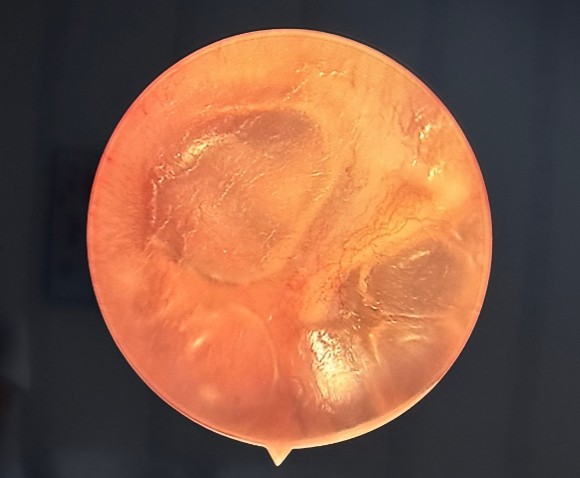

● Отоскопия (осмотр ушей): Выявлены признаки двустороннего воспаления. Наружные слуховые проходы широкие. Справа обнаружено скудное гнойное отделяемое. Барабанные перепонки с обеих сторон были гиперемированы (покрасневшие) и отечны, что является типичными симптомами острого воспалительного процесса.

На фото отоскопии слева визуализируется гиперемированная и выбухающая барабанная перепонк, за барабанной перепонкой визуализируется гнойное отделяемое.